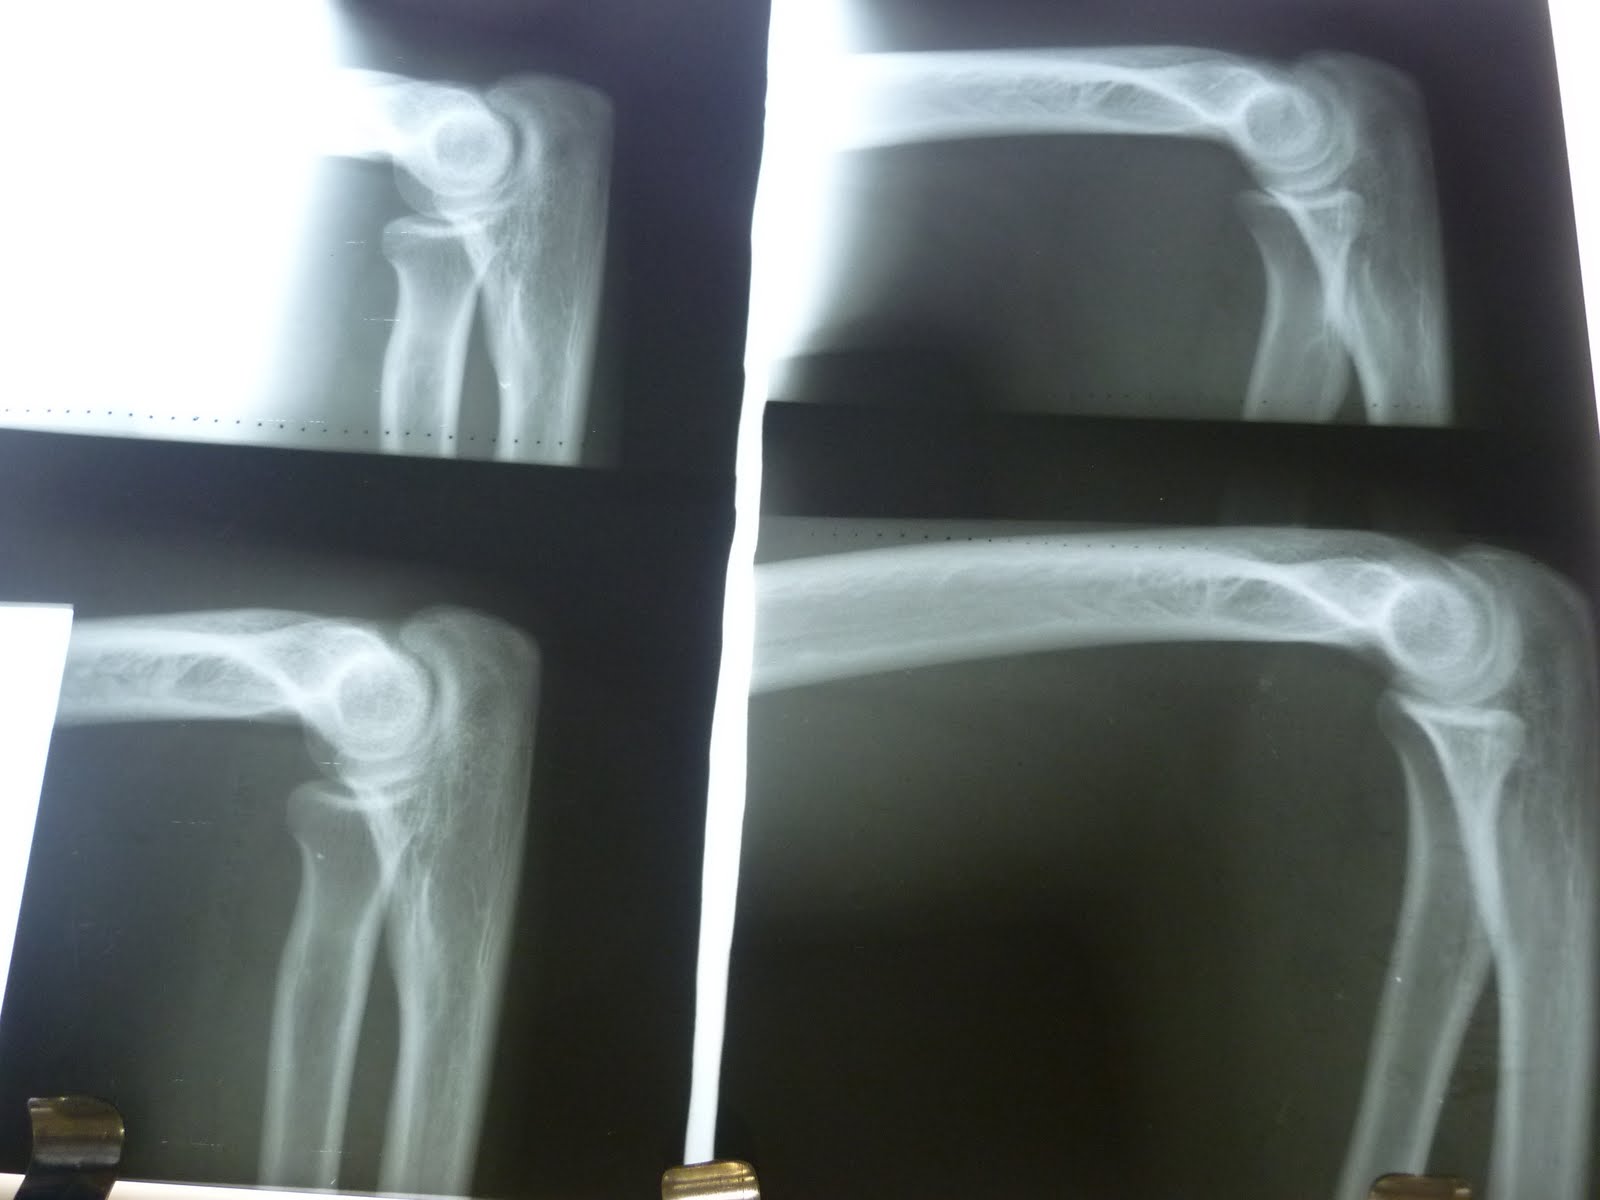

DICAS DE RADIOLOGIA: COMO AVALIAR A QUALIDADE DA RADIOGRAFIA DE SEIOS

Source: dicasradiologia.blogspot.com